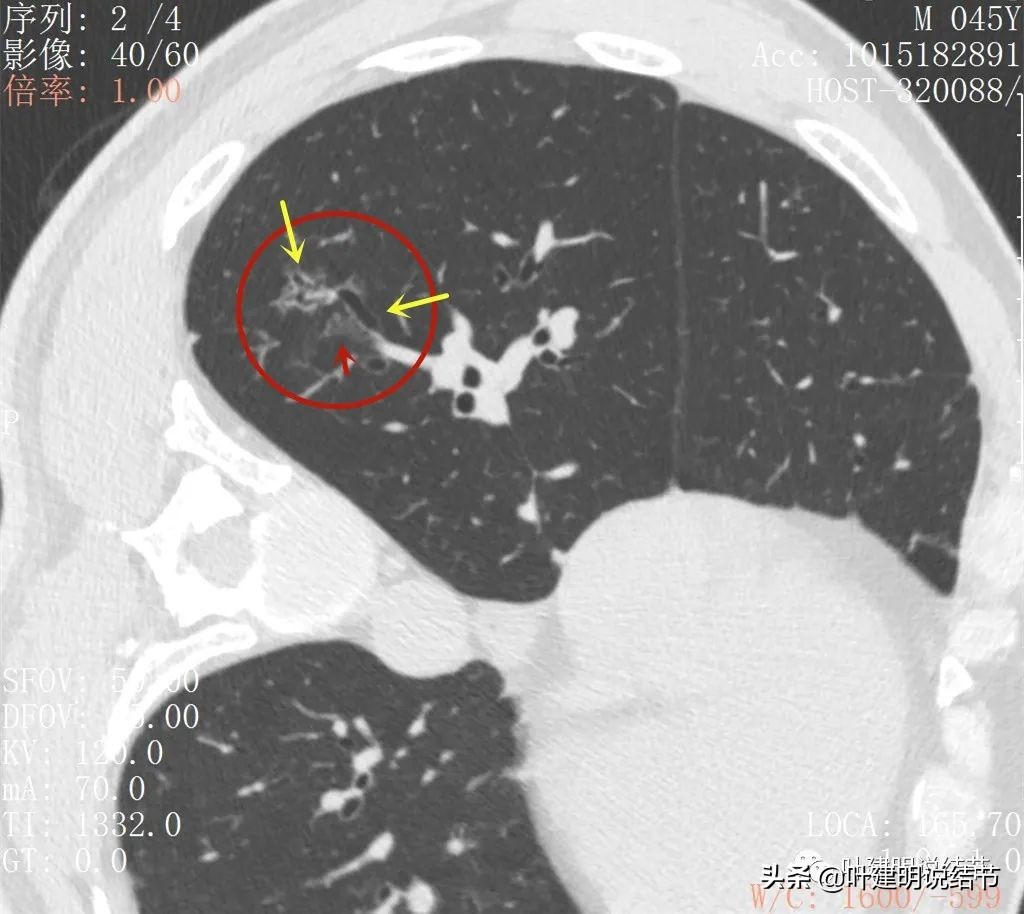

2022年5月复查靶扫描的图像:

病灶出现,磨玻璃密度,非圆形或类圆形,感觉比较散

病灶虽然不密,但轮廓较清,磨玻璃成分明显,感觉偏向恶性

病灶有少许实性成分(粉色箭头)

病灶似有血管进入(桔色箭头),而且血管异常增粗,整体病灶轮廓较清,似有分叶,中间有空泡征呈蜂窝状